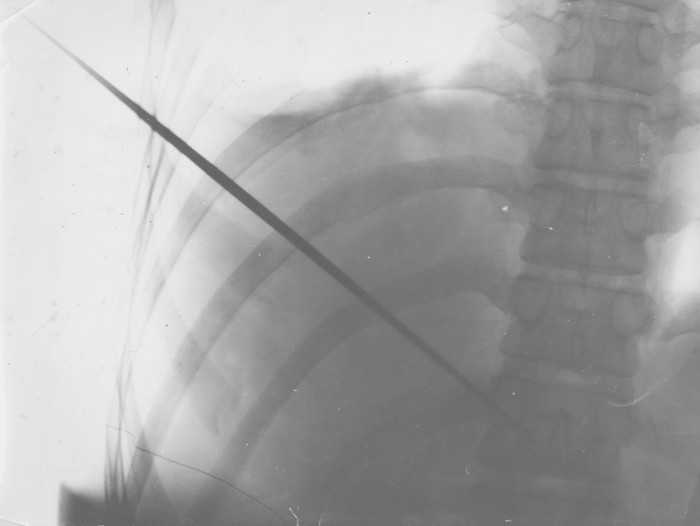

Để kiểm chứng cho màn trình diễn của mình, Mirin Dajo đã yêu cầu các bác sĩ chụp X-quang cơ thể mình với nguyên một thanh kiếm đâm xuyên qua ngực. Sau khi quan sát phim chụp, các chuyên gia đều xác nhận rằng thanh kiếm quả thực đã đi từ bên này qua bên kia cơ thể. Sau khi kết quả đã rõ mười mươi, Mirin Dajo nhẹ nhàng rút kiếm ra và nhanh tay ấn chặt vào vết thương trên người. Có lẽ đó là lí do giúp máu không chảy. Đặc biệt, Mirin Dajo chẳng cần dưỡng thương khi vẫn tiếp tục các công việc khác một cách bình thường.

Nhìn tấm phim X-quang này, không ai dám nói màn trình diễn của Dajo là trò bịp nữa.